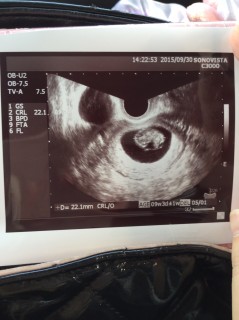

一気に人の姿になっていてビックリ! 8w6dだと思っていたら大きさから4日早まって9w3dになりました。 CRL22.1mm